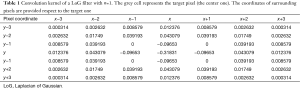

This formula returns the values of a convolution kernel that is a matrix with values that have to be convolved above the initial pixels values of an image. The returned values of a convolution kernel matrix are similar to the Table 1, where x and y represent the coordinates respect to the target pixel (the center grey colored one) and σ=1.

Full table